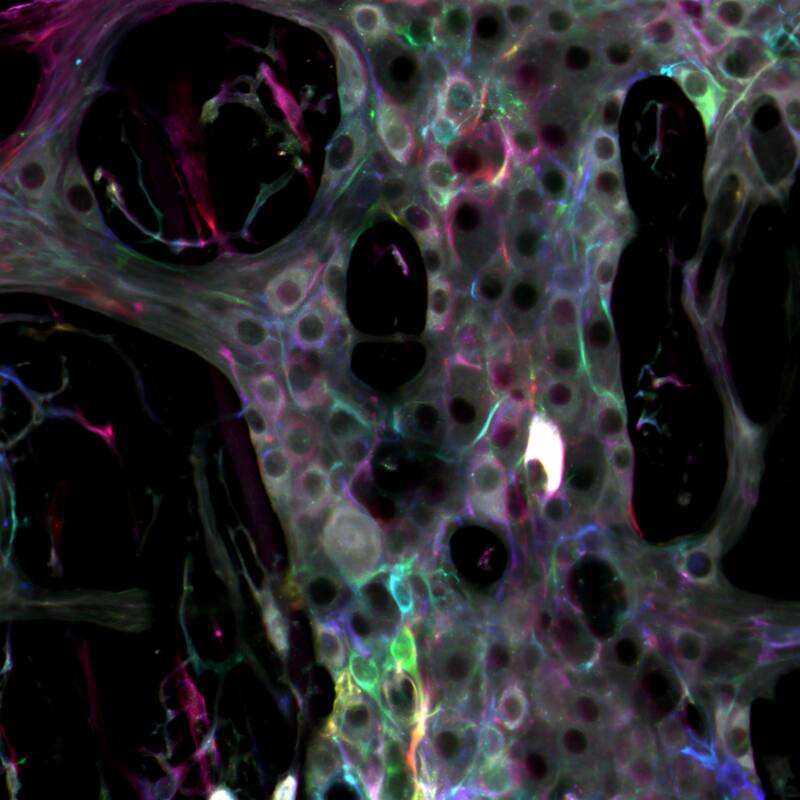

“Es como un segundo cerebro en nuestro intestino”, afirmó Gulbransen. “Es una extensa red de neuronas y glía que recubre nuestros intestinos”.

Las neuronas son el tipo de célula más familiar, y son famosas por conducir las señales eléctricas del sistema nervioso. Las glías, por otro lado, no son eléctricamente activas, lo que ha hecho que sea más difícil para los investigadores descifrar lo que hacen estas células. Una de las principales teorías fue que las células gliales brindan apoyo pasivo a las neuronas.

Gulbransen y su equipo han demostrado ahora que las células gliales desempeñan un papel mucho más activo en el sistema nervioso entérico. En la investigación publicada en línea en la revista Proceedings of the National Academy of Sciences, los investigadores revelaron que la glía actúa de forma muy precisa para influir en las señales que transmiten los circuitos neuronales. Este descubrimiento podría ayudar a allanar el camino hacia nuevos tratamientos para enfermedades intestinales como el síndrome del intestino irritable que afecta entre un 10% y 20% a la población chilena.

“Si pensamos en este segundo cerebro como en un computador, la glía es el chip que funciona en la periferia”, dijo Gulbransen. “Son una parte activa de la red de señalización, pero no como las neuronas. La glía modula o modifica la señal”.